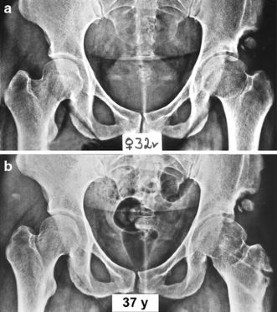

Fig. 4